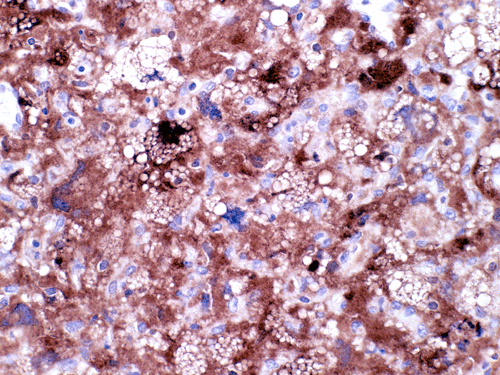

The mass consists of a mixture of spindle cells and clear cells. There is a rich vascular network (Panel A) with sinsusoidal dilatation but no anastomosis of the vascular channels. The endothelial cells appear lean and not protruding into the vascular channel. The clear cells appear to have foamy cytoplasm (̃ in Panel B). The nuclei are hyperchromatic and may appear slighly grooved or lobuated. On immunohistochemistry, the foamy cells are strongly reactive for inhibin (Panel C). These cells are also reactive for S100 protein (Panel D) and neural specific enolase (Panel E) . No immunoreactivity for epithelial membrane antigen (EMA) is observed (Panel F). The tumor is not immunoreactive for cytokeratin.

The truely helpful immunohistochemical marker in this case is inhibin. S100 protein, neural specific enolase, and EMA are rather non-specific.

Microscopically, hemangioblastomas consist of foamy to clear stromal cells interspersed with endothelium lined vascular channels. Clear vacuoles within the stromal cells can be stained with Oil red-O or similar stain if applied to frozen sections. The stromal cells stain strongly for epidermal growth factor receptor (EGFR) and platelet-derived growth receptor factor alpha (PDGF-alpha) 12 and inhibin 13. The stromal cells are typically negative for epithelial membrane antigen (EMA) and cytokeratin 14. In a small number of cases, the stromal cells express glial fibrillary acidic protein (GFAP) 7, 14 and S100 protein 14. These staining results should be interpreted with case as they may represent entrapped glial cells. The admixed capillaries will stain for with typical endothelial markers (Factor-VIII and others) 15, but the stromal cells are typically negative for the endothelial markers. To this date, the pathogenesis and cell origin of hemangioblastomas is not certain.